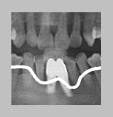

08.01.15 처음 내원 때, 사진

: 타 병원에서 임플란트 2개를 심었는데,

후방의 하나는 빠져버렸고, 전방 부위에도

잇몸뼈의 손상이 컸음.

그래서, 제거 수술 후 인공뼈이식을 통해,

잇몸뼈를 재생시킨 후,

2개의 임플란트 재식립을 계획하였다.